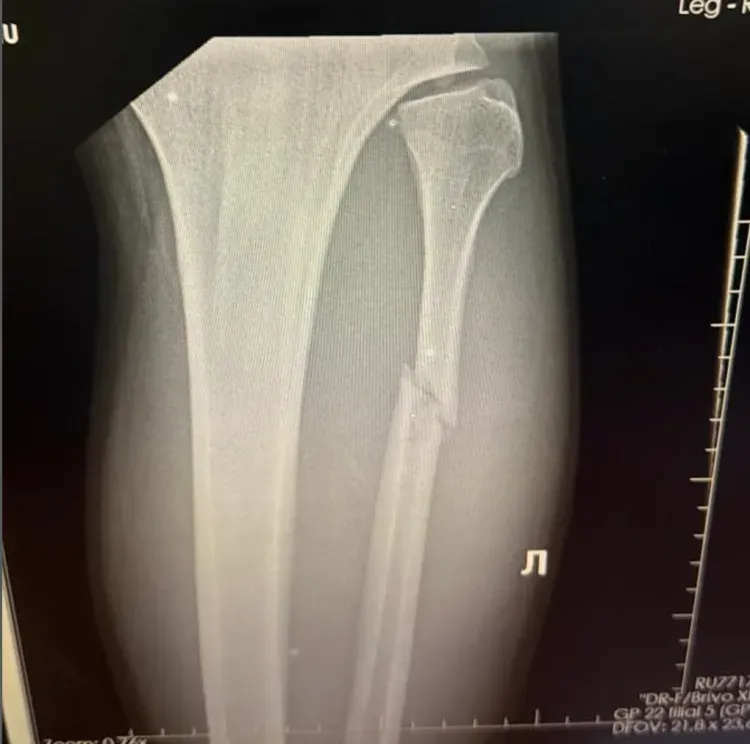

Ce n'est qu'après une visite chez le médecin et une radiographie que la vérité a éclaté, choquant Walker lui-même. « Quand le médecin m'a montré l'image, je n'y croyais pas. Je me suis dit : "Quoi ? Ma jambe est cassée ?" »